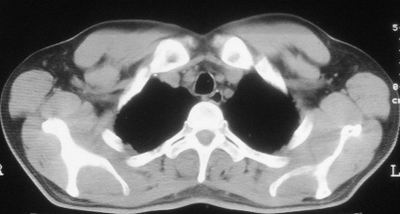

患者,男,44岁,糖尿病4年余,近期消瘦、乏力。化验检查:总胆红素26.33(参考值:5.1-17.2u mol/l),直接胆红素:6.4(参考值:0-4.3u mol/l),谷-丙转氨酶(alt):843(参考值:<40u/l),hbsag(+),抗hbs(-),hbeag(-),抗-hbe(+),抗-hbc(+)。

2\\少量腹水

1.双肺急性粟粒型肺结核;2.少量腹水.